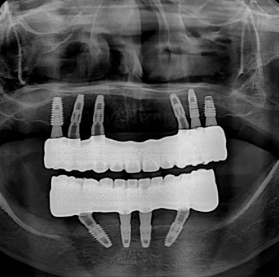

ALL IMPLANT VS FULLARCH

전체임플란트 vs 풀아치

한눈에 보는 치료법 비교

특징 디지털 풀아치 전체 임플란트 전통 틀니

씹는 힘 우수 (자연치 80%) 최우수 (90~100%) 미흡 (20~30%)

뼈 이식 거의 불필요 필요한 경우 많음 해당 없음

편안함 고정식, 이물감 없음 고정식, 내 치아 같음 탈착식, 이물감 있음

치료 기간 단기간 (약 2~3개월) 장기(6개월~1년) 비교적 빠름

장기 안정성 매우 높음 (10년 후 93% 이상) 매우 높음 재제작 필요 (5~7년 주기)

전체 비용 높음 매우 높음 낮음(중)